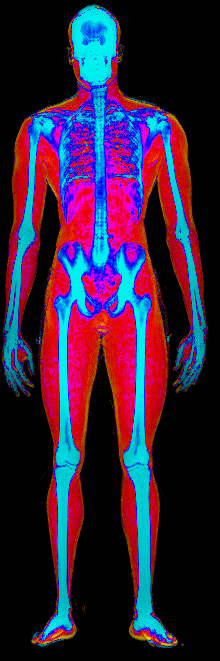

This page features real, anonymized DEXA scan images from BodyStats clients, organized by gender and body fat percentage in 5% increments. DEXA (Dual-Energy X-ray Absorptiometry) is the clinical gold standard for measuring body composition — far more accurate than scales, calipers, or visual estimates.

Each colorized scan shows the distribution of fat tissue (shown in warmer colors) and lean tissue (cooler colors) throughout the body. Compare your own DEXA scan to others in your range, or see what different body fat levels actually look like on a scan.

Male DEXA Scans by Body Fat %

10 to 15% body fat